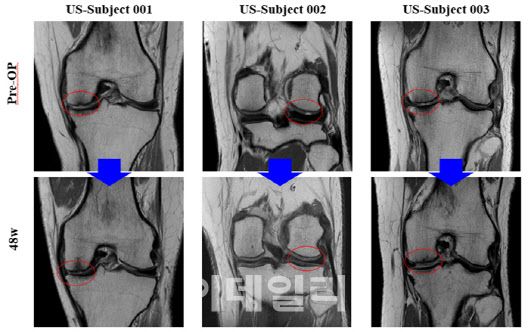

For the U.S. Phase 2 trial, Bio Solution released MRI images from select patients, visually confirming cartilage regeneration in defect areas up to 48 weeks post-procedure. Key evaluation metrics, including KOOS (pain and mobility improvement), VAS, and IKDC scores, also demonstrated consistent improvement over 24 and 48 weeks.